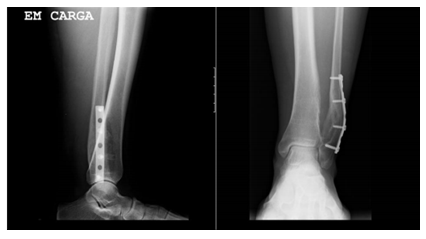

She was submitted to lesion excision and osteosynthesis with syndesmosis tibio-peroneal and fibula stabilization with plate and 2 trans-syndesmotic screws (Figure 4).

Figure 4 X-Ray post-excision of the lesion demonstrating osteosynthesis with plate and screws.

Histopathological examination confirmed the diagnosis of osteochondroma. At 2 months after surgery it was performed the extraction of two trans- syndesmotic screws (Figure 5), and after 18 months it was removed all material of osteosynthesis (Figure 6).

Figure 5 X-Ray after removing two trans-syndesmotic screws.

At 3 years after surgery, the patient shows a complete recovery, with full mobility and no residual pain and radiologically without evidence of recurrence (Figure 6).

Figure 6 X-Ray after 3 years lesion excision.